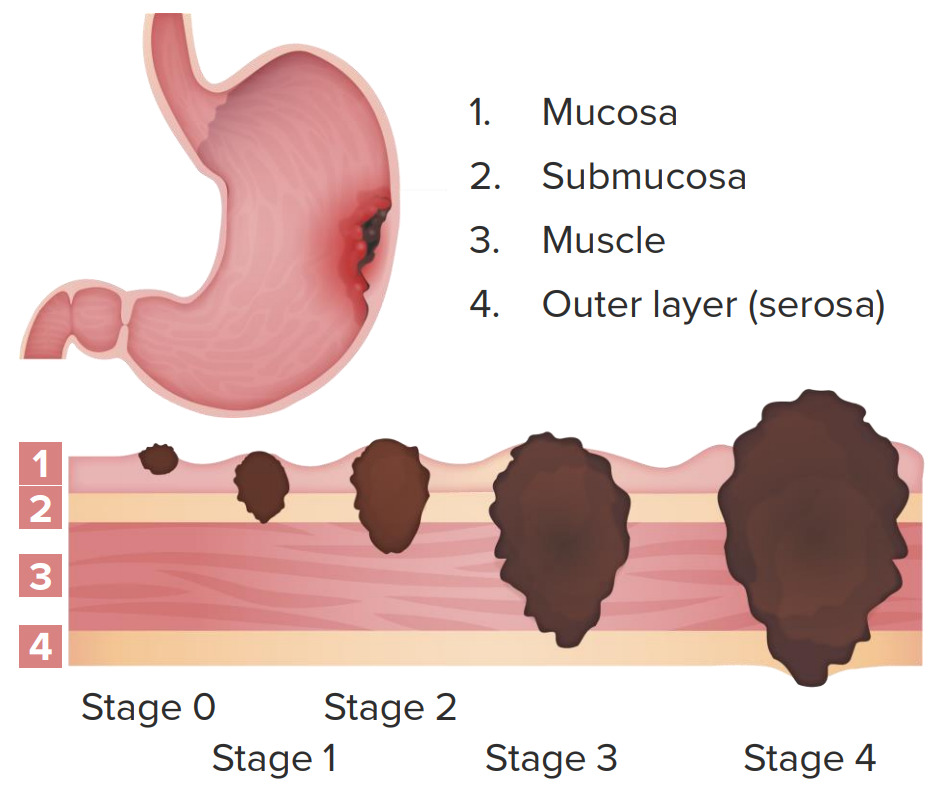

Stomach Cancer | Symptoms, Causes, Stages, Treatment and Survival Rates

Stomach Cancer | Symptoms, Causes, Stages, Treatment and Survival Rates

Cancer in the Stomach|Causes|Symptoms|Stages|Treatment|Survival Rate

Stages Of Gastrointestinal Cancer | herxheim.de

Stage 4 Stomach Cancer. What is advanced cancer? | by Zeeva Clinic | Medium

Stage 4 Stomach Cancer. What is advanced cancer? | by Zeeva Clinic | Medium

Stage 4 Stomach Cancer. What is advanced cancer? | by Zeeva Clinic | Medium